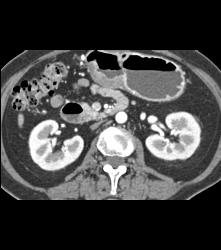

Antral Carcinoma